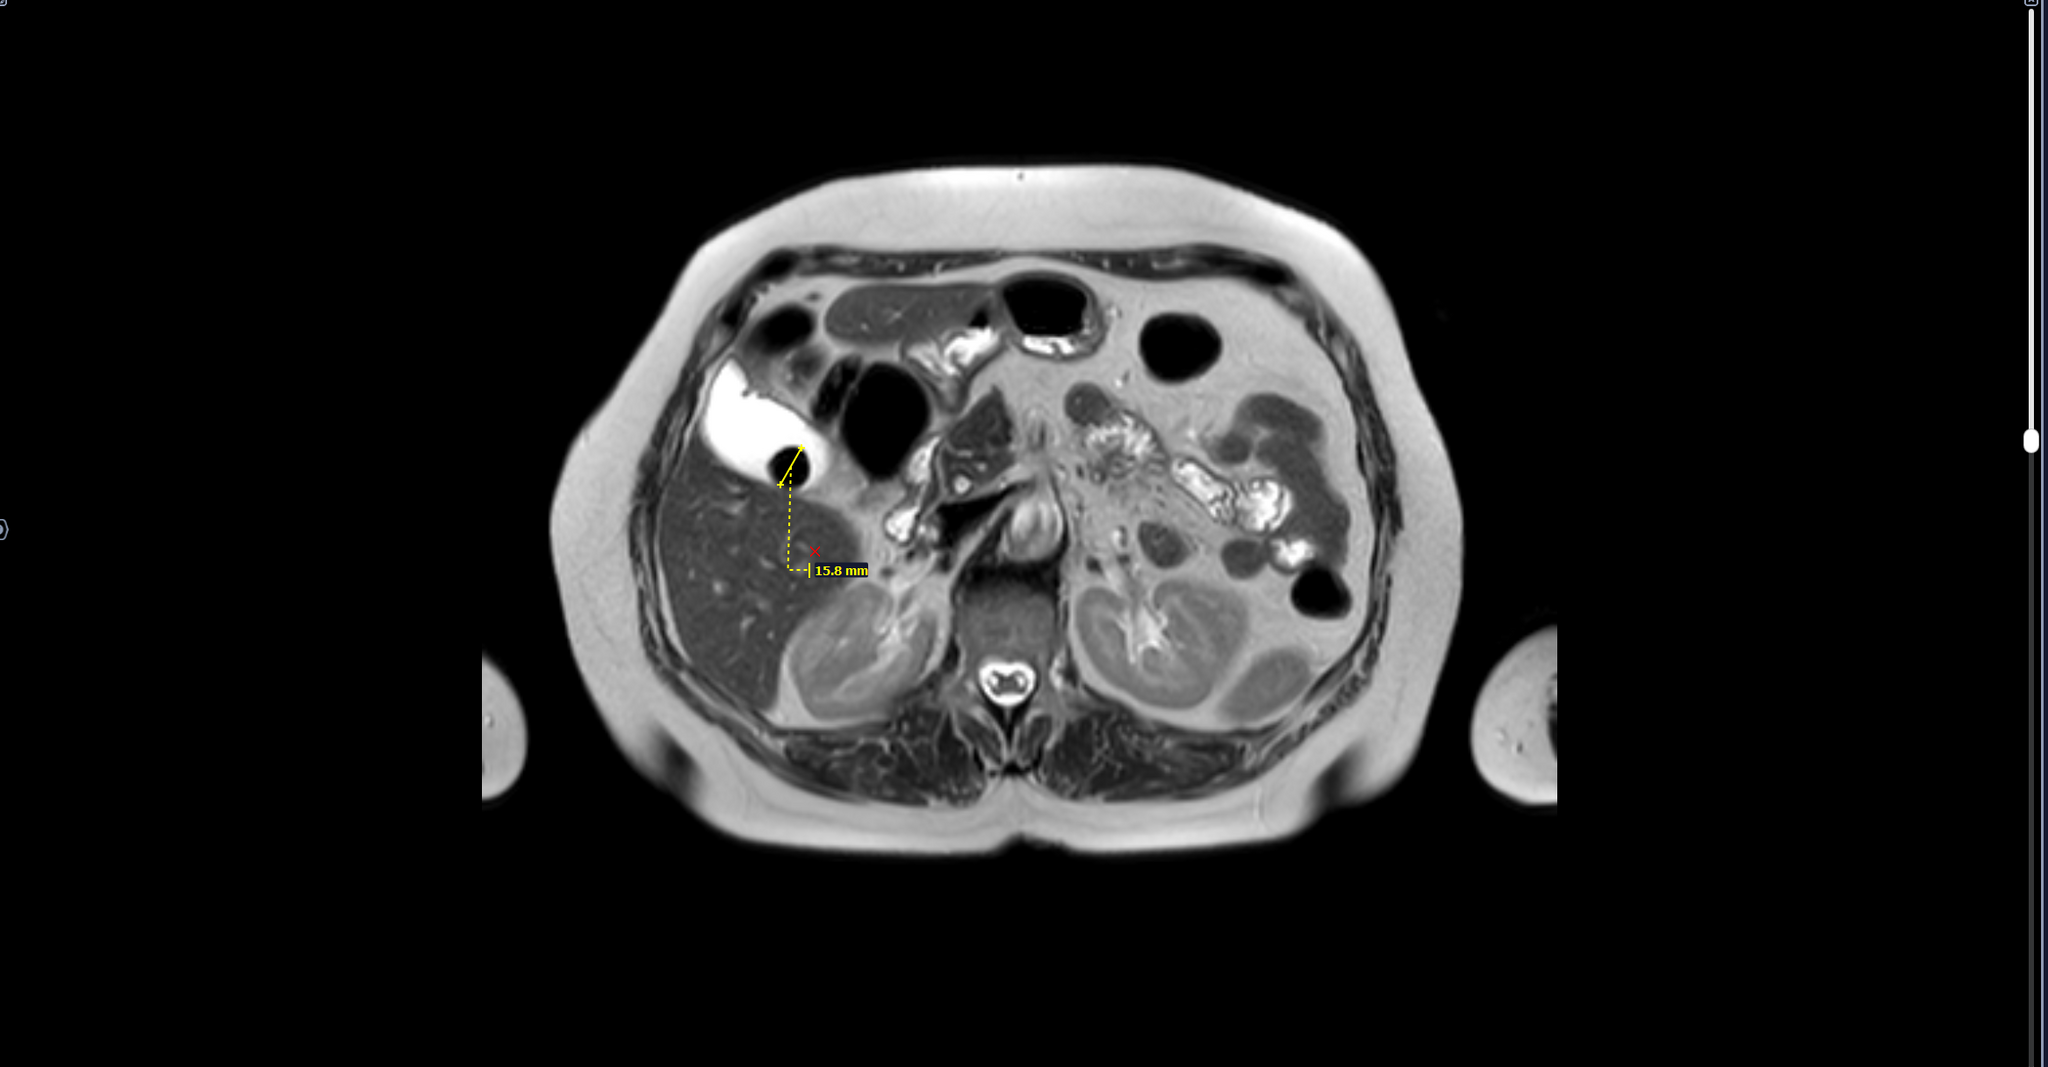

В тему к посту: камень желчного пузыря выявленный на МРТ, диаметром 15 мм.